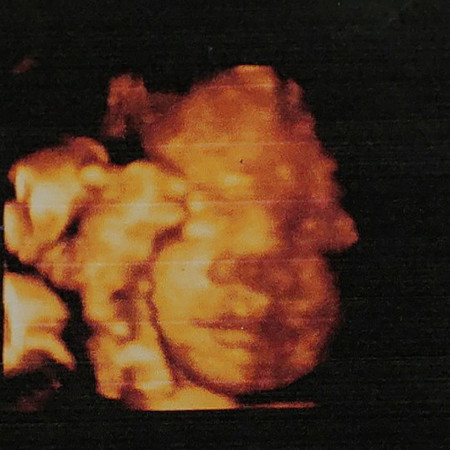

29w pak